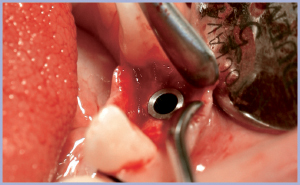

Si inserisce in anestesia locale un impianto Exacone® 3,3×10 mm (figg. 3, 4) in tecnica monofasica, utilizzando un tappo di guarigione con piattaforma standard.

- Fig. 3

- Fig. 4